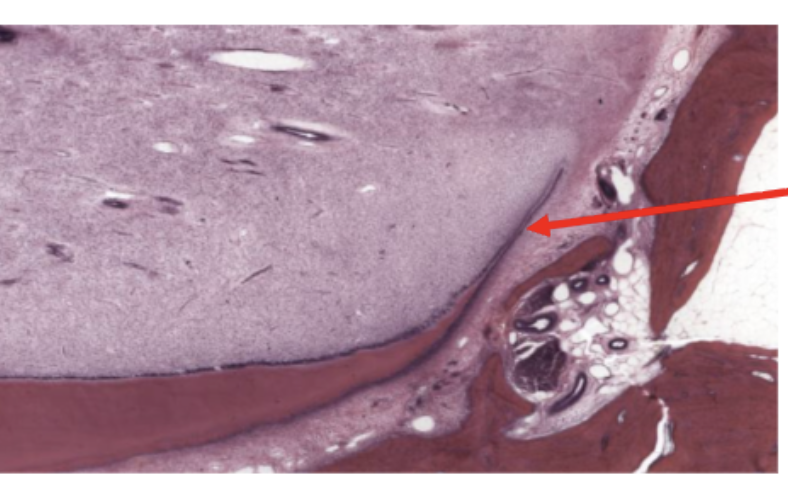

ID the region

cementoenamel junction

ID the tissue

acellular cementum

Cellular cementum